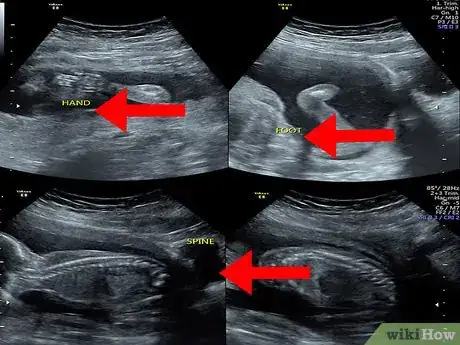

2Spot the baby. Your baby will also look grey or whitish and will be located within the amniotic fluid (the dark area inside of the womb). Look at the area within your amniotic fluid to try to make out the outline and features of your baby.

- The details that you see in the image will depend on the stage of your pregnancy. For example, at eight weeks, the fetus will look something like a gummy bear or a baked bean; at 12 weeks, you may only be able to identify the head of your baby; while at 20 weeks, you may be able to see the spine, eyes, feet, and heart.[8]